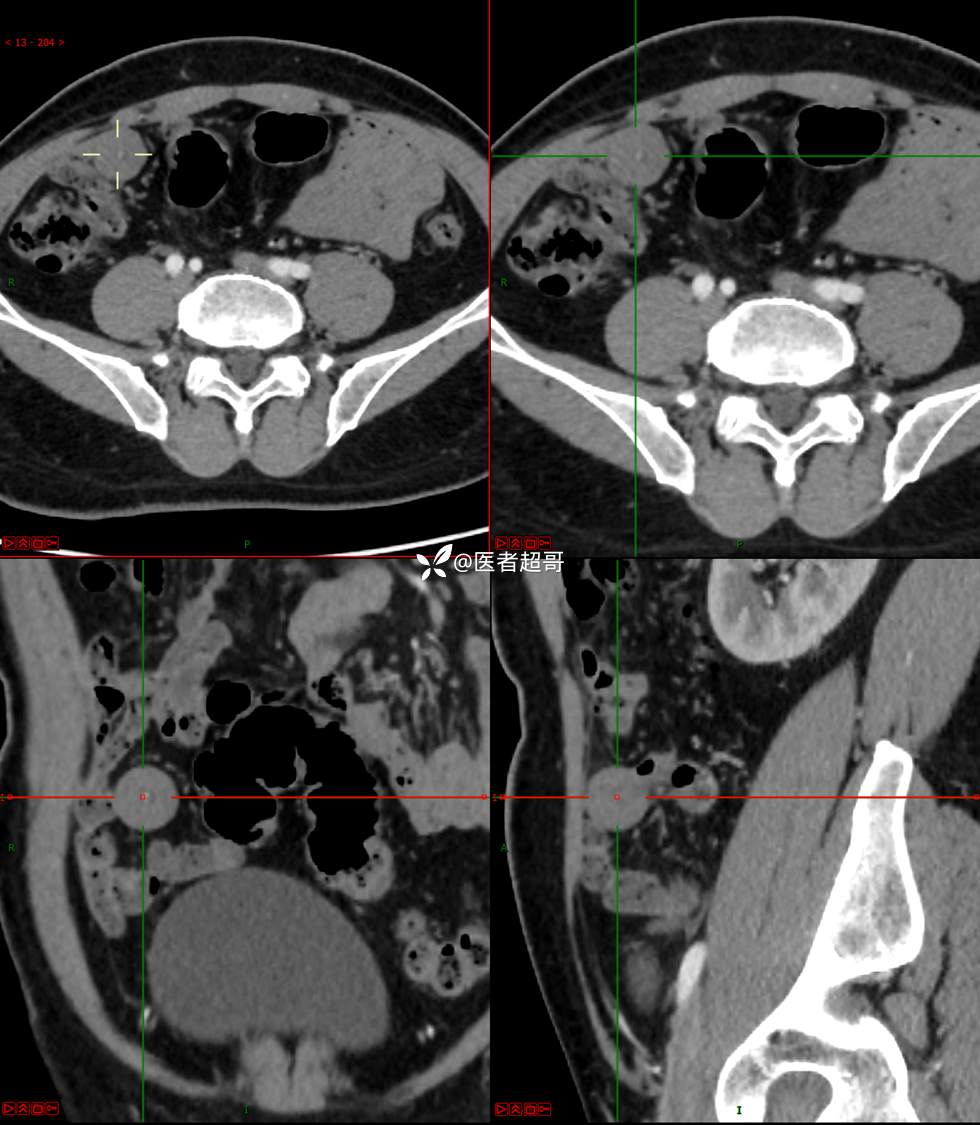

【影诊笔记747】结节不大,挺有意思的,做手术了,请赏析!

男,48岁 0200608 01

主诉:腹痛1月余。

现病史:患者1月余前无明显原因及诱因出现腹痛,脐周为著,为持续性隐痛,无发热,无恶心、呕吐,无腹泻,伴反酸,无胸闷、憋气,无呕血、黑便,至我院门诊就诊,查肝胆胰脾肾彩超诊断:肝胆胰脾双肾未见异常,下腹部实性团块,建议进一步检查,血淀粉酶46U/L,血常规未见明显异常,自服“肠炎宁”药物治疗,效果欠佳,现患者为行进一步治疗,门诊以“腹痛待查 腹腔肿物”收入院。患者自发病以来,神志清,精神可,饮食、睡眠可,大小便正常,体重较前无明显减轻。